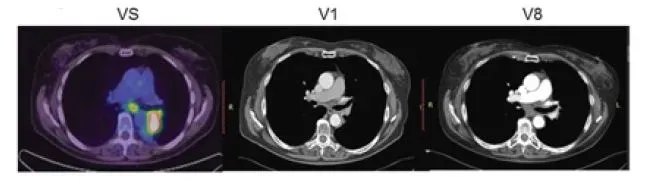

上图展示联合疗法中一个典型的成功案例,治疗1-2个月后复查,肺部肿瘤完全消失,并且疗效已经保持了18个月。

PE-CT扫描显示患者接受NK细胞治疗后

在医生的建议下,患者接受NK细胞治疗2个周期,二次治疗间隔3个月。随访3年,PET扫描发现没有发生复发的情况,并且患者对治疗耐受良好,没有免疫相关的不良反应。并且在结肠癌手术后3年的临床随访中,患者可以很好地进行日常活动。